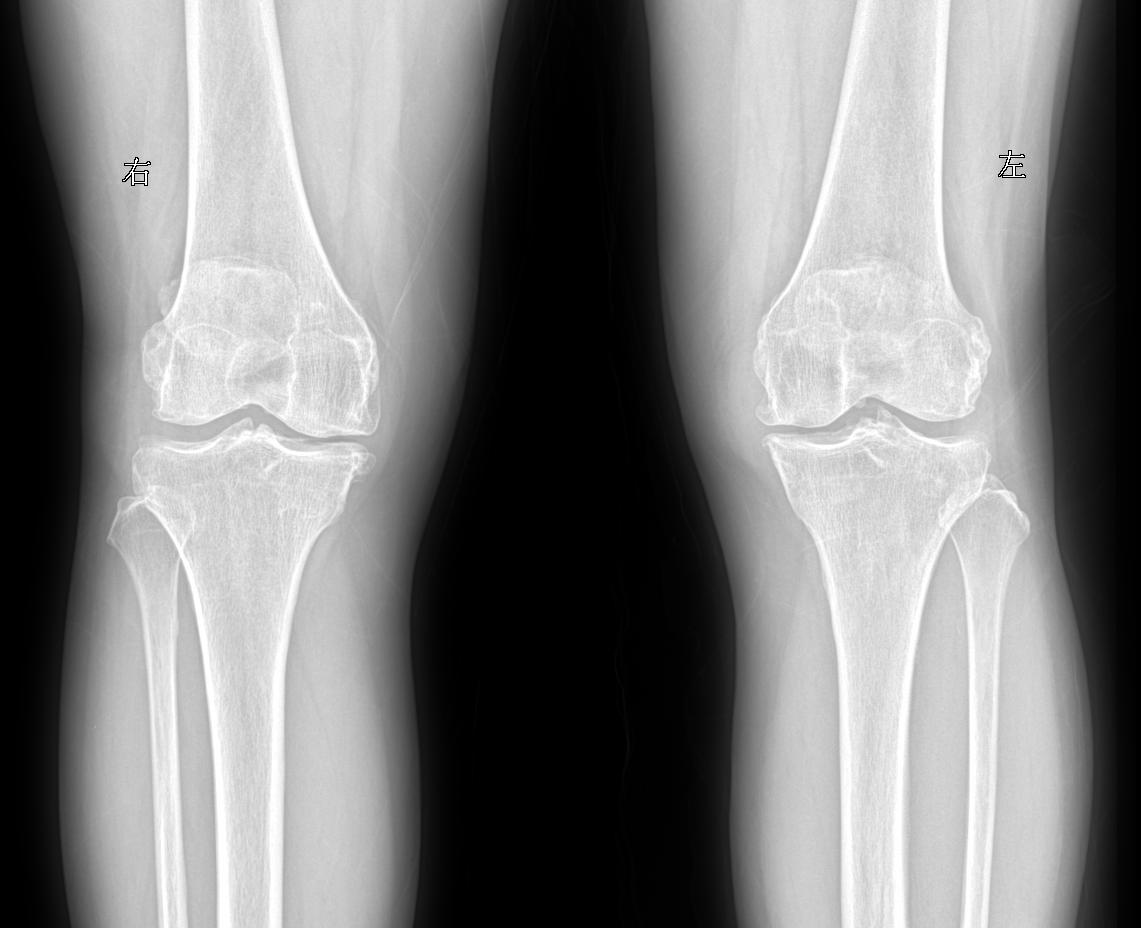

患者女 74岁行走时膝关节疼痛就诊

2025-02-28 16:07